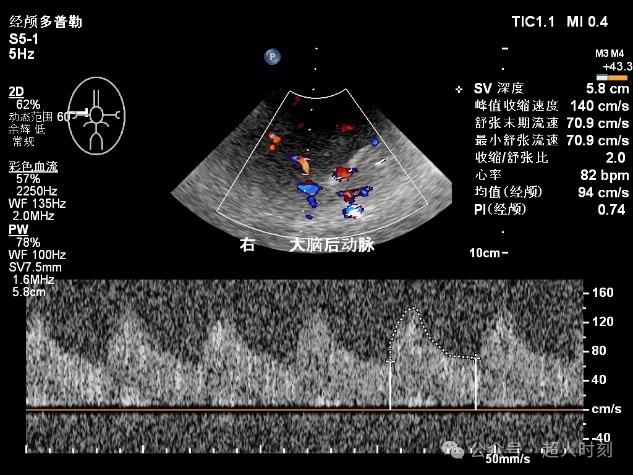

图5e 左大脑中动脉狭窄频谱(VP:178cm/s)